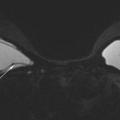

En IRM mammaire :

– des séquences spécifiques (dédiées silicone) suppriment le signal de l’eau et de la graisse, rendant possible le diagnostic précis de rupture ou de siliconome ;

– pour une analyse concomitante de la glande mammaire : injecter du gadolinium.